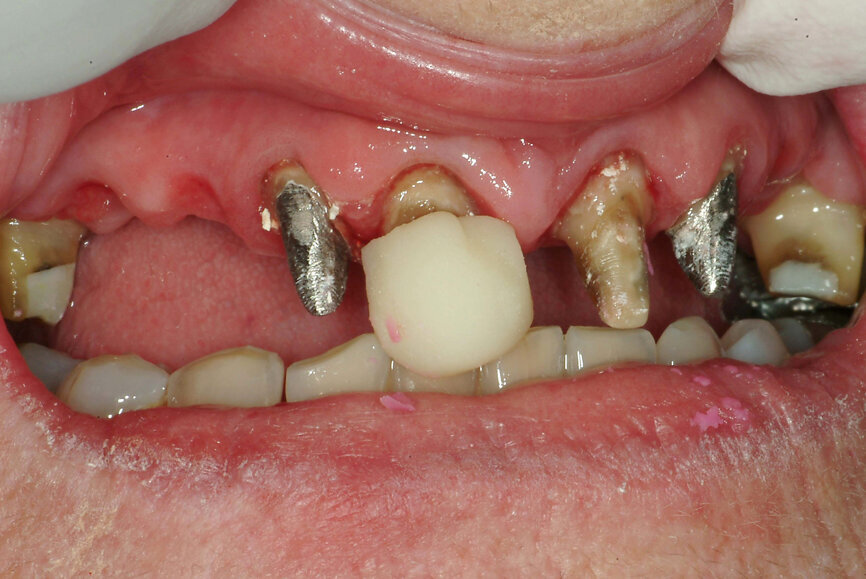

Fig. 25: Digital centric relation recording at the desired vertical

dimension of occlusion of all existing mandibular teeth, in preparation for a fixed complete denture.

The technique for recording the CR position can be performed using analogue (Figs. 22 & 23) or digital methods (Figs. 24–27).